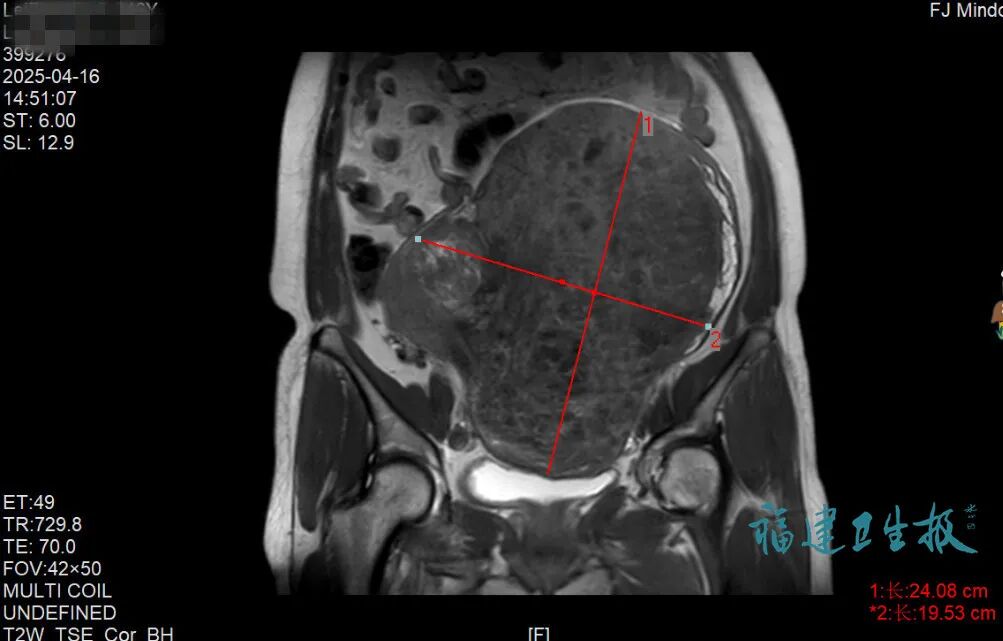

“這幾年肚子越來越大,腰帶都換了三四條?!?雷女士原本以為只是普通發(fā)胖,直到半月前因意外受傷做檢查,才被超聲結(jié)果驚出冷汗——盆腔里竟藏著一個直徑超過20厘米的巨大占位實性腫塊!

寧德市閩東醫(yī)院婦科主任醫(yī)師何彩平說:“這個肌瘤相當(dāng)于足月胎兒大小,已嚴(yán)重壓迫內(nèi)臟器官?!?經(jīng)進(jìn)一步診斷,確診為多發(fā)性子宮肌瘤。